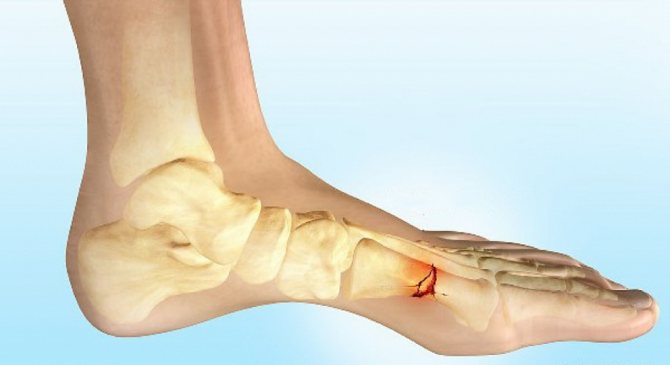

Свои причины имеются и при переломе лодыжек, наглядно они представлены на фото. Чаще всего стопа подворачивается кнутри или кнаружи с нагрузкой по оси конечности собственного веса. Повредиться кость может в результате удара или падения на кость тяжелого предмета.

- повреждения лодыжек.

Область лодыжек

- боль и отечность концентрируются в голеностопе,

- нога в нижней части увеличивается в размере,

- движение голеностопа невозможно, активность ноги ограничена,

- гематома либо открытая рана,

- стопа развернута в неестественное положение,

- пострадавший не может опираться на ногу.